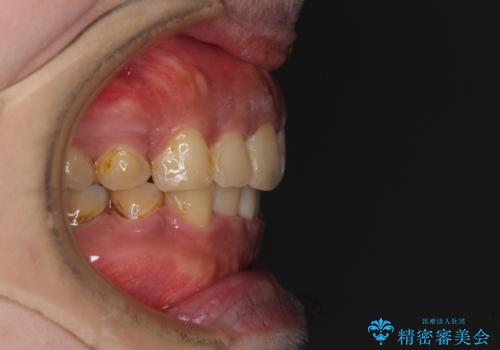

- 口元の突出感と上下前歯のでこぼこを気にして来院された患者様です。

上下前歯部叢生のスペース獲得のため、上下顎左右小臼歯各1歯(計4本)を抜歯して、矯正治療を行うこととしました。

口腔内の清掃性に問題があり、虫歯のリスクが極めて高かったため、短期で治療を終えることを最優先に治療を進めました。